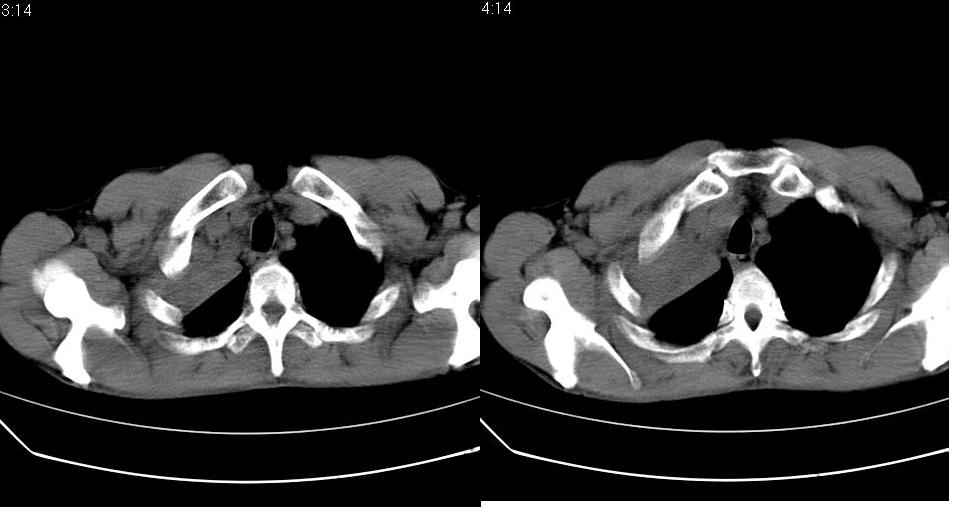

男 58岁 咳嗽,无明显不适.

右侧肺门肿块,右上叶不张,右上胸廓塌陷,气管纵隔右移,纵隔内有些小淋巴结,考虑中央型肺癌,作个支气管纤维镜取个病理吧,鳞癌的可能性大

右肺上叶中央型ca,右上叶支气管起始部变狭窄,致右肺不张,纵隔及腋窝淋巴结肿大,请结合纤维镜检查.